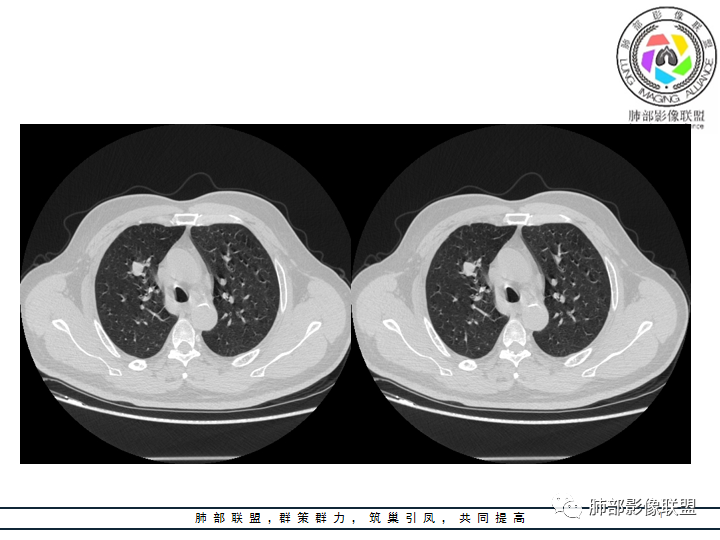

影像资料

老年男性患者,长期吸烟史,没有呼吸系统临床表现。胸部CT示右肺上叶实性密度结节影,密度均匀,未见空洞及钙化,边缘较光整,未见分叶及毛刺。血管影旁现侧出,支气管进入并截断,不均匀强化。

恶性病灶需要排除的有神经内分泌癌(大细胞癌、小细胞癌、类癌)、鳞癌、淋巴瘤样上皮癌、淋巴瘤等等。